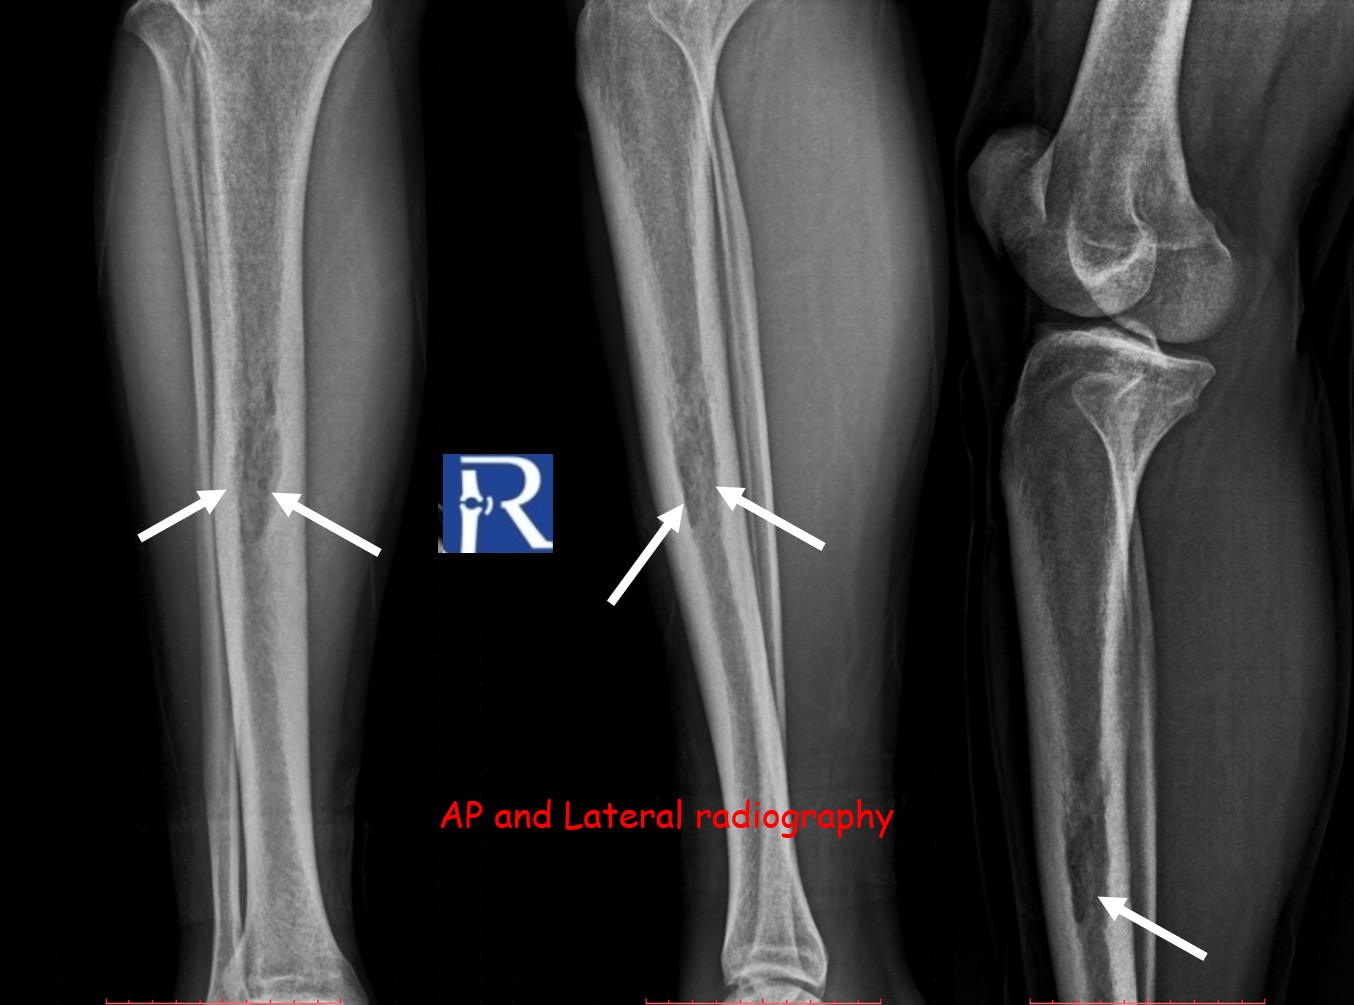

Plain radiography of the right tibia demonstrated a permeative lytic lesion at the mid-diaphysis, exhibiting aggressive characteristics but no periosteal reaction.

The lesion exhibited limited cortical destruction, yet extensive soft-tissue extension. Multiple conglomerate inguinal and pelvic lymph node enlargements were also identified, demonstrating signal characteristics similar to those of the primary lesion.

These imaging findings—particularly the absence of periosteal reaction, intermediate T2 signal, and marked DWI restriction—favored the diagnosis of lymphoma over Ewing sarcoma.